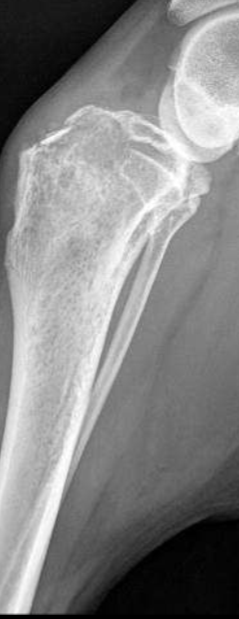

What type periosteal reaction?

Solid

Describe a solid periosteal reaction?

bone completely fills the area under the reaction

More chronic, the more solid/mineralized

Surface can be smooth or undulating

Non-aggressive

Callus

What type of periosteal reaction?

Lamellated periosteal reaction

Describe a lamellated periosteal reaction

Layered or onion skin appearance

Indicates a cyclic or intermittent process

More aggressive than solid, smooth bone usually associated with a benign process